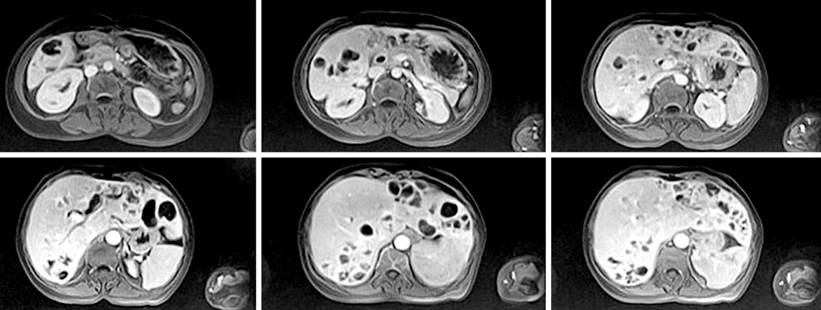

En los últimos 5 años fue evaluada en diferentes centros de salud, y se registró la realización de estudios de gabinete, rastreo digestivo (gastropatía eritematosa universal, con Helicobacter pylori +) y colonoscopía sin hallazgos patológicos. Además, se llevó a cabo una resonancia abdominal en la que se adquirieron cortes axiales y coronales en las imágenes en T2, T1, T2FAT-SAT, FASE y FS sin y con medio de contraste, en las que se evidenció el hígado aumentado de tamaño y morfología preservada, con la presencia de múltiples lesiones quísticas distribuidas al azar en ambos lóbulos hepáticos y captación anular del medio de contraste (Figura 1). Se realizó también una colangiorresonancia en la que se observó una dilatación importante de la vía biliar intrahepática, específicamente hepática izquierda, y una lesión quística de bordes regulares, bien definida, que condicionó una dilatación de la vía biliar extrahepática (Figura 2). Luego de la inyección del medio de contraste se observó un defecto de repleción, sugestivo de coledocolitiasis en el conducto hepático izquierdo. Se realizó una biopsia que no reportó hallazgos sugestivos de malignidad, por lo que se decidió manejar su cuadro clínico agudo solo con antibioticoterapia (carbapenémicos) y seguimiento periódico de la lesión.

Figura 1 Resonancia abdominal de cortes axiales y coronales. Hígado con 22 cm en eje longitudinal, bordes regulares, con presencia de múltiples lesiones quísticas en ambos lóbulos hepáticos con captación anular del contraste. Fuente: expediente médico del paciente.